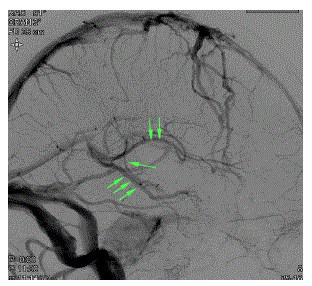

Veia atrial medial (seta simples), veia talamoestriada (setas duplas) e veia basal de Rosenthal (setas triplas).